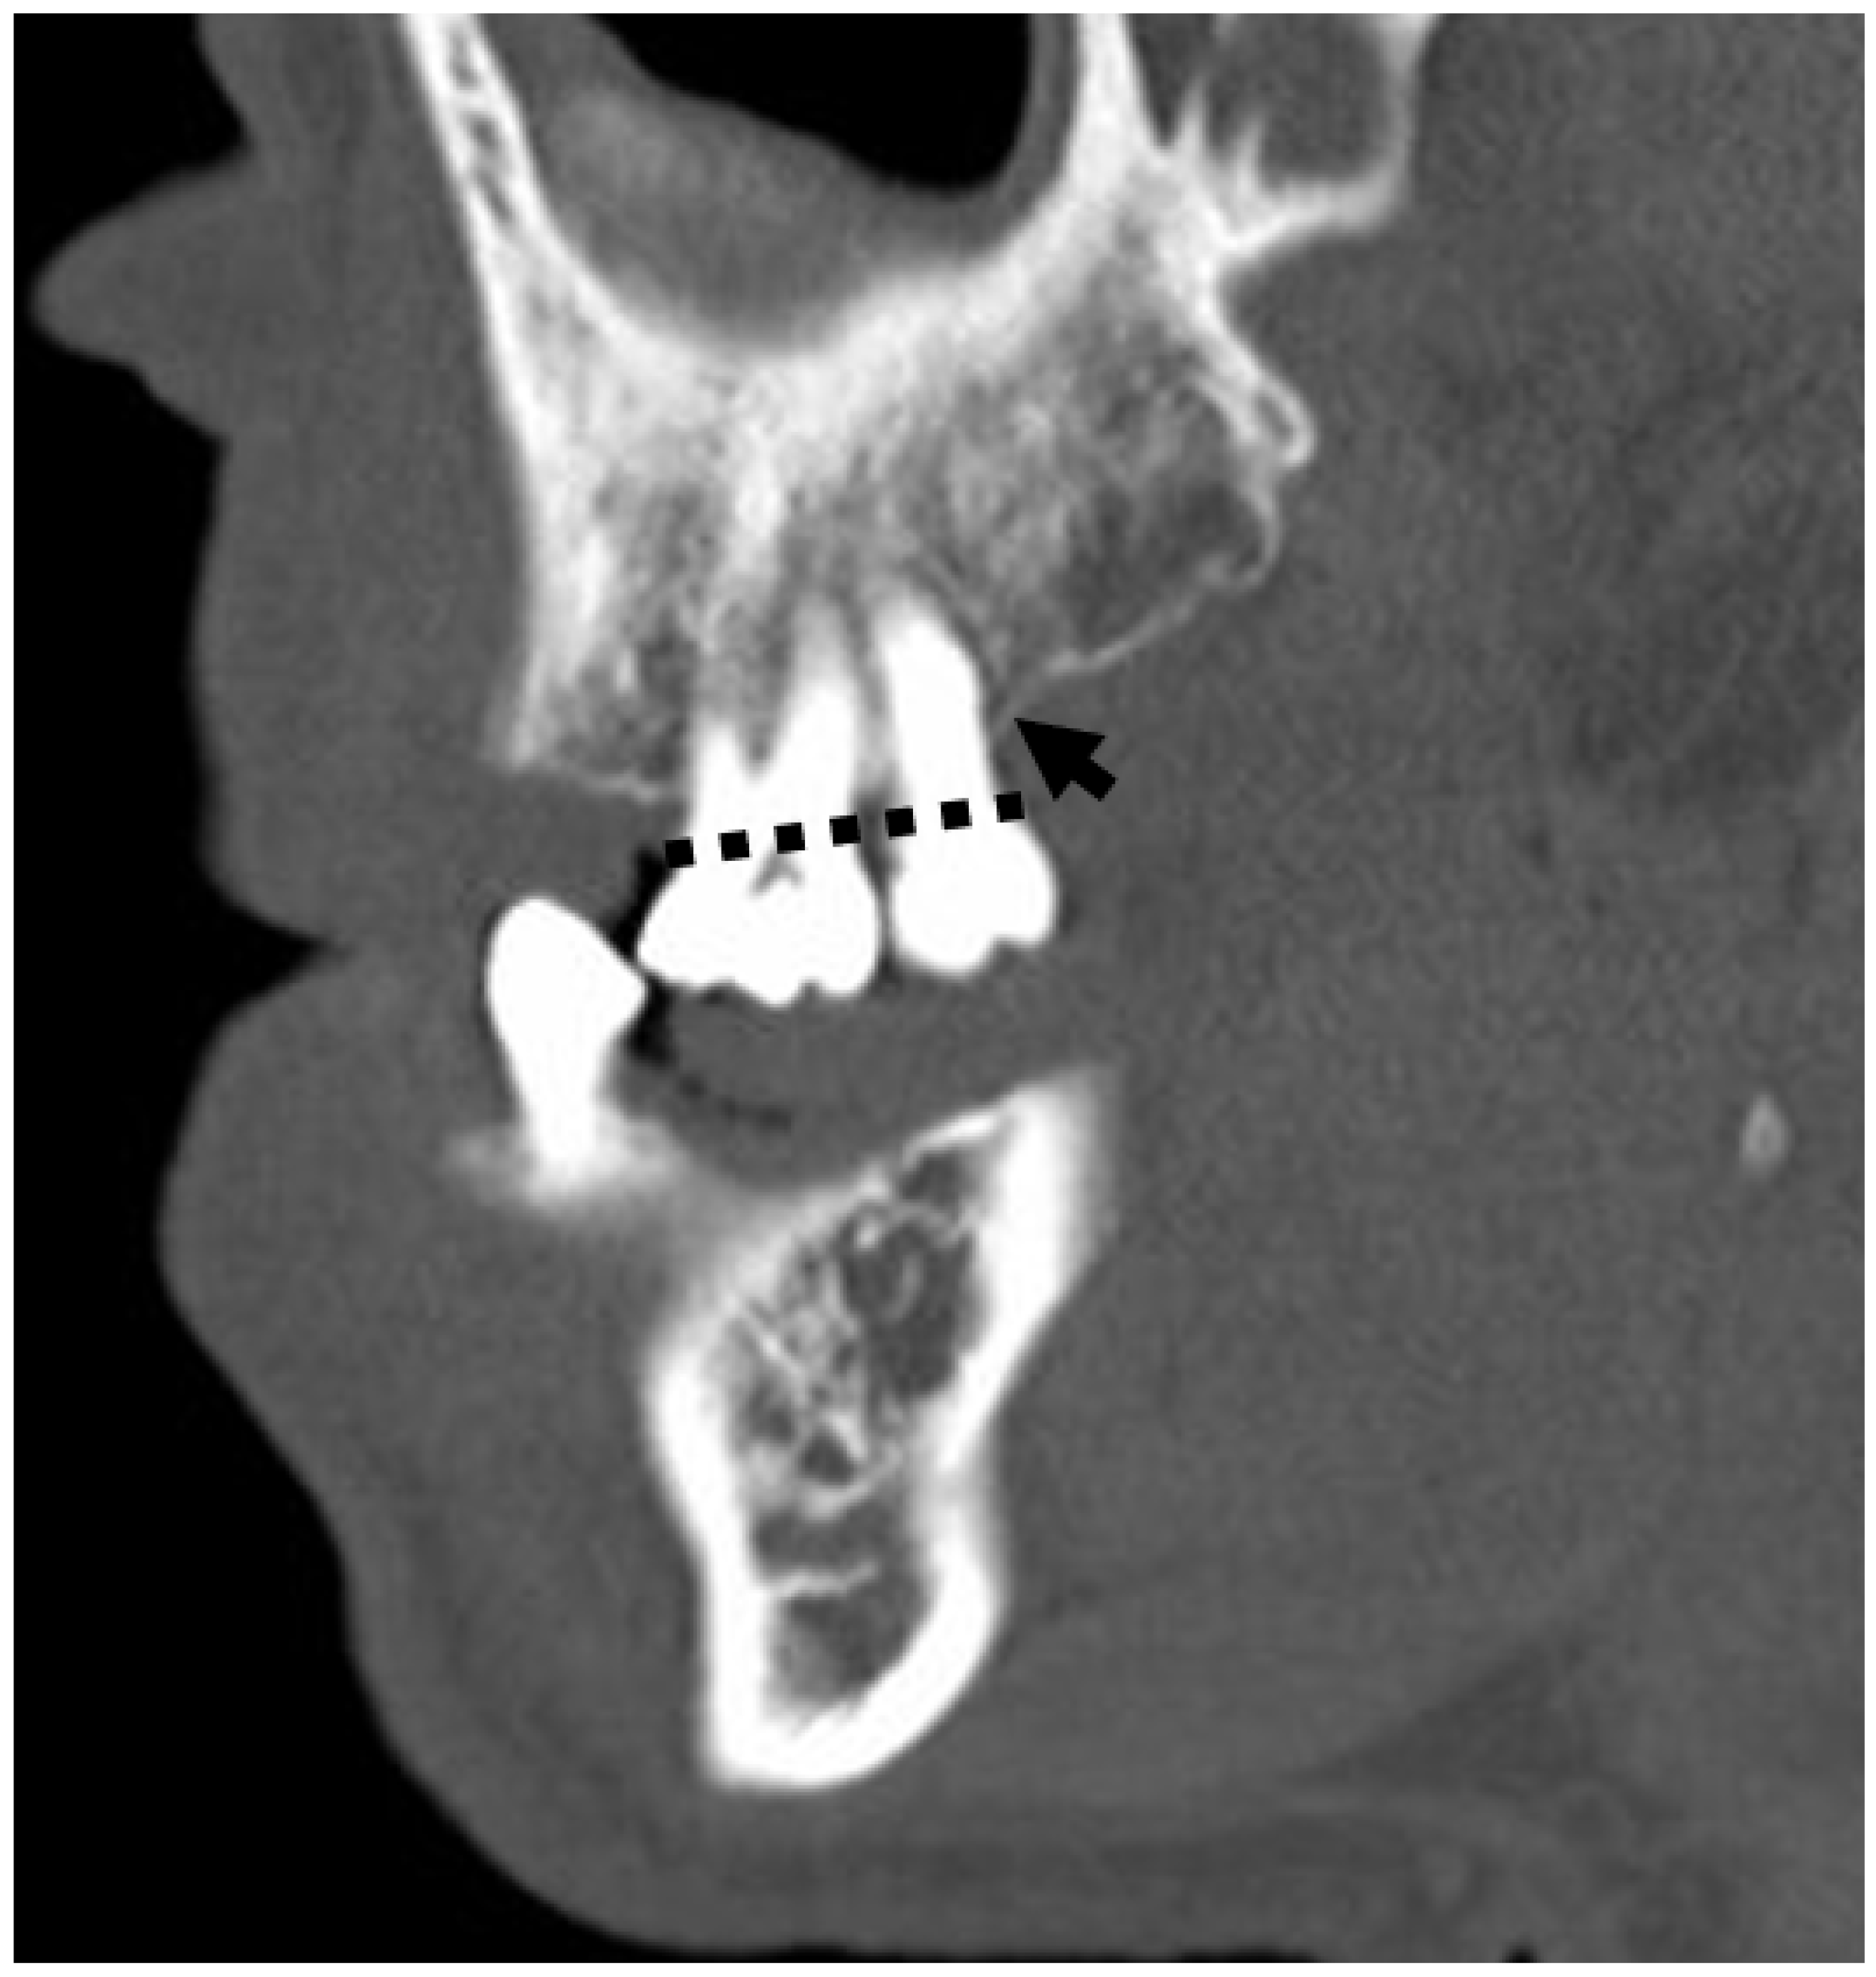

3.5. Anatomical and Imaging Correlations to Odontogenic Infectious Disease

3.5.2. Dental Decay Radiologic Correlations

3.5.4. Periodontal Disease Radiologic Correlations